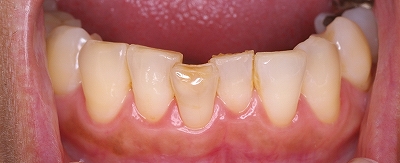

40歳を過ぎた女性です。

幼い頃から下顎前歯の歯並びがずっと気になっていました。

人生にゆとり、生活に余裕ができた今、歯並びを治す事に

しました。

今更などという事ではなく。

これからの長い人生に変化をもたらしてくれると信じています。

きれいな美しい歯並びで新しい人生のスタートです。